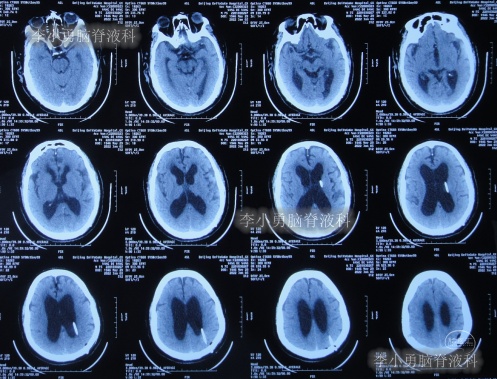

出院后再次转住入当地的第1家医院进行康复治疗,在该院康复治疗半年多的时间,不但没有持续好转,反而再次腰疼,走路不稳,且还出现了尿失禁的持续加重症状;治疗期间曾6次查头部影像(图-13、图-14、图-15、图-16、图-17)均示脑积水不断加重的趋势。

图-13:2021年5月22日头部核磁

图-14:2021年6月2日头部核磁

图-15:2021年7月24日头部核磁

图-16:2021年8月28日头部核磁

图-17:2021年9月28日头部CT